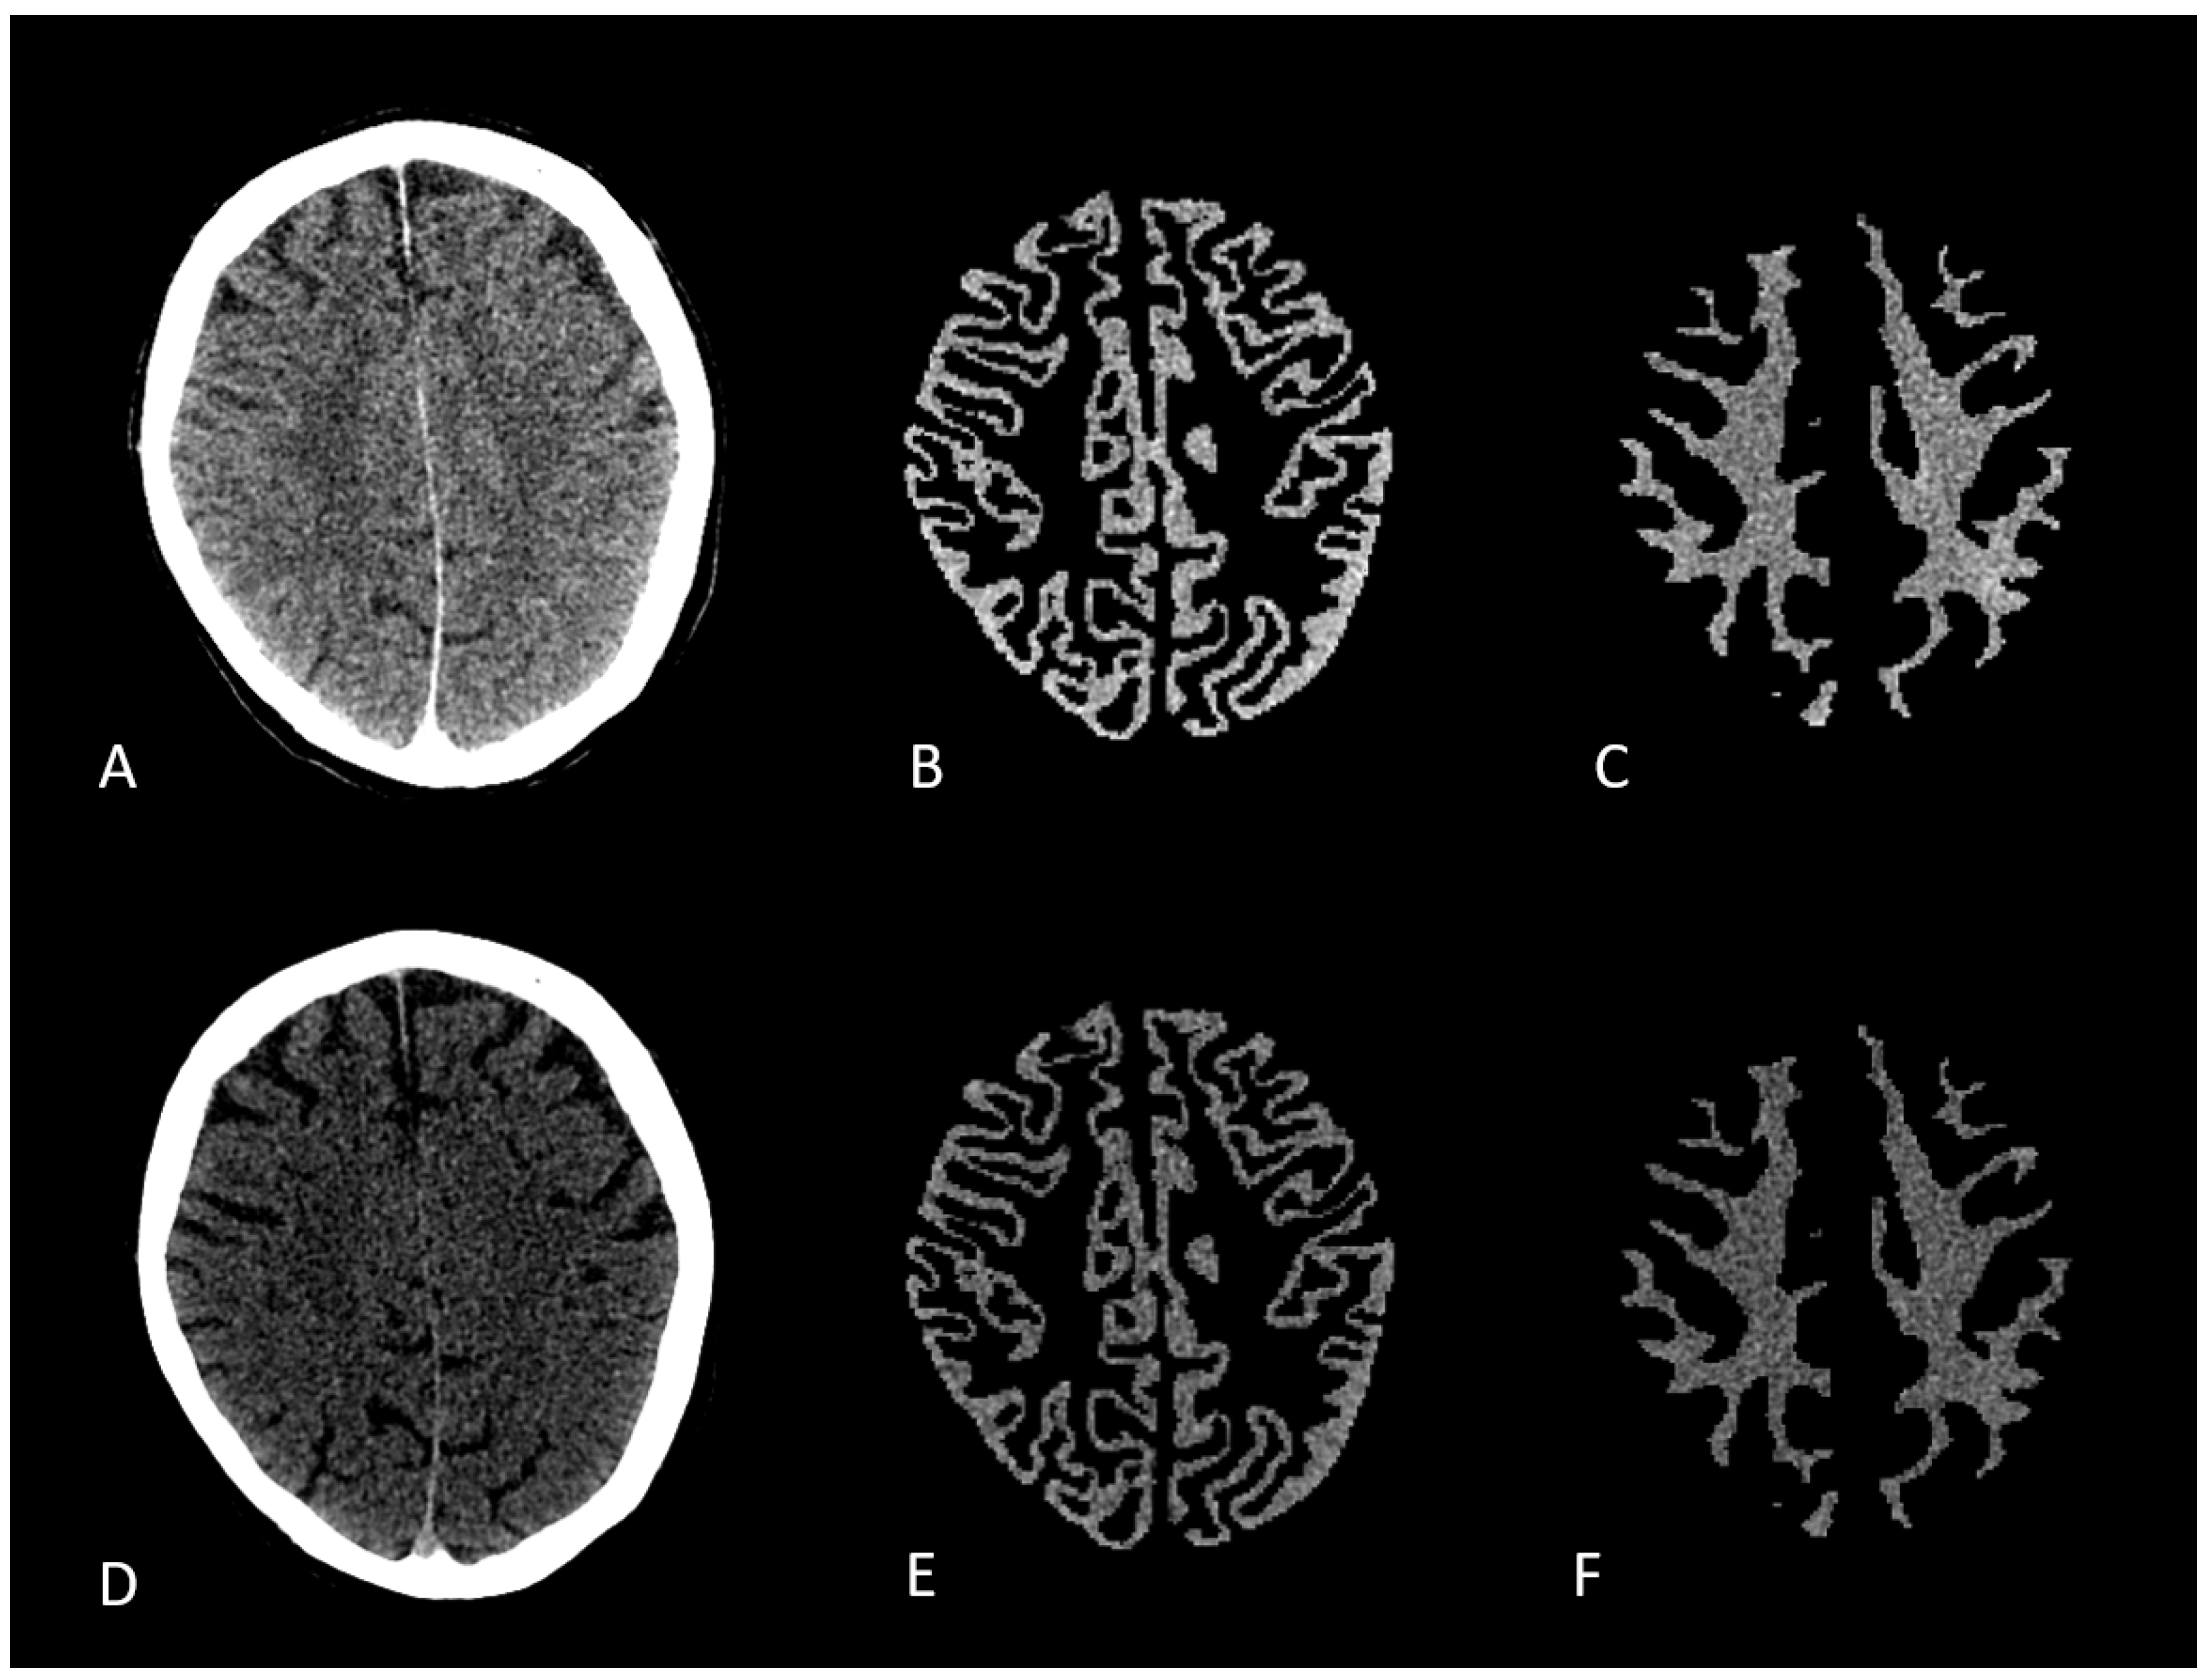

2.2. Image Acquisition and Post Processing

2.3. Image Conversion

- Grams, A.E.; Djurdjevic, T.; Rehwald, R.; Schiestl, T.; Dazinger, F.; Steiger, R.; Knoflach, M.; Gizewski, E.R.; Glodny, B. Improved visualisation of early cerebral infarctions after endovascular stroke therapy using dual-energy computed tomography oedema maps. Eur. Radiol. 2018, 28, 4534–4541. [Google Scholar] [CrossRef] [PubMed]